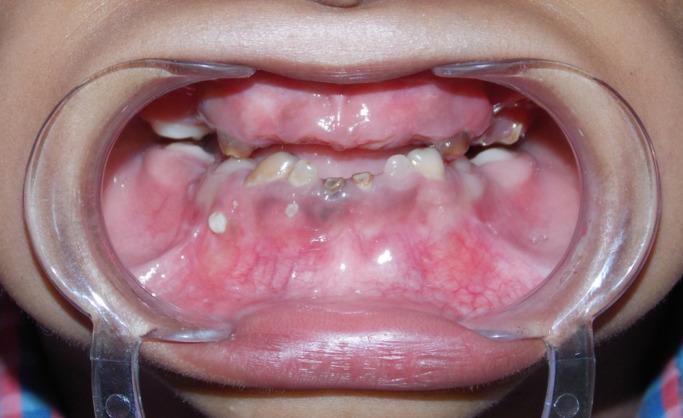

Tricho-dento-osseous syndrome (TDO), an uncommon form of ectodermal dysplasia is an autosomal dominant genetic disorder which is characterized by inherited defects in tissues arising from epithelial-mesenchymal interaction. Genetic studies have revealed that it is caused by mutation in the DLX3 gene. TDO presents with a great phenotypic heterogeneity and studies have suggested that this heterogeneity is the result of environmental factors or other genetic modifiers. In this article, we report a case of TDO in which the child had typical clinical features of hair, teeth and bone defects, as seen in TDO. Parents of the child were unaffected. Genetic analysis of the child revealed mutation in DLX3 gene. The child also showed precocious eruption of the permanent molars, a clinical feature which has been rarely reported. We suggest that the precocious eruption seen in TDO is probably due to a markedly increased osteoblastic activity. Tricho-dento-osseous syndrome, DLX3 gene, precocious eruption.

毛发-牙齿-骨综合征(TDO)是一种罕见的外胚层发育不良形式,是一种常染色体显性遗传病,其特征是上皮-间充质相互作用产生的组织存在遗传性缺陷。基因研究表明,它是由DLX3基因突变引起的。TDO表现出很大的表型异质性,研究表明这种异质性是环境因素或其他基因修饰因子的结果。在本文中,我们报告了一例TDO病例,该患儿具有TDO典型的毛发、牙齿和骨骼缺陷临床特征。患儿的父母未受影响。对该患儿的基因分析显示DLX3基因发生突变。该患儿还出现了恒牙早萌,这是一种很少有报道的临床特征。我们认为TDO中出现的恒牙早萌可能是由于成骨细胞活性明显增加所致。毛发-牙齿-骨综合征、DLX3基因、恒牙早萌。